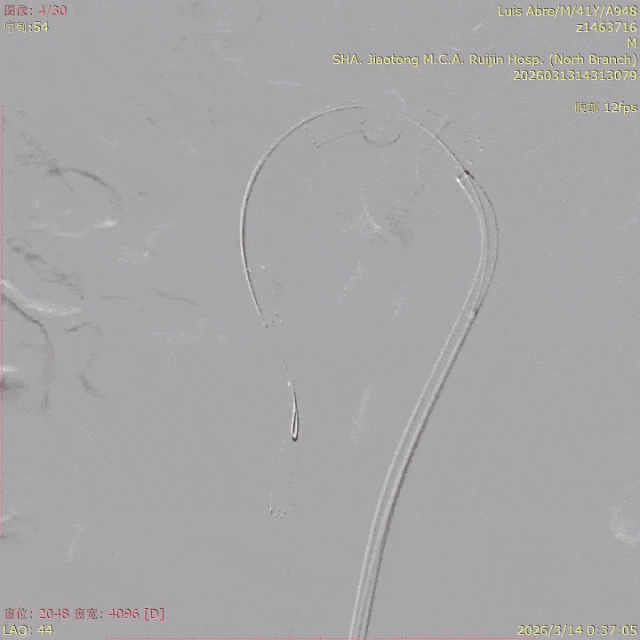

在嘉定院区介入中心,血管外科冯家烜医生团队为危在旦夕的Luis实施了“肠系膜上动脉支架置入术”,撑开了原本已经闭塞的肠系膜上动脉血流通道。

术前造影

术后造影

团队进一步通过IVUS(血管内超声)技术确认:支架形态良好、贴壁完美,夹层影完全消失,各分支血管显影清晰。